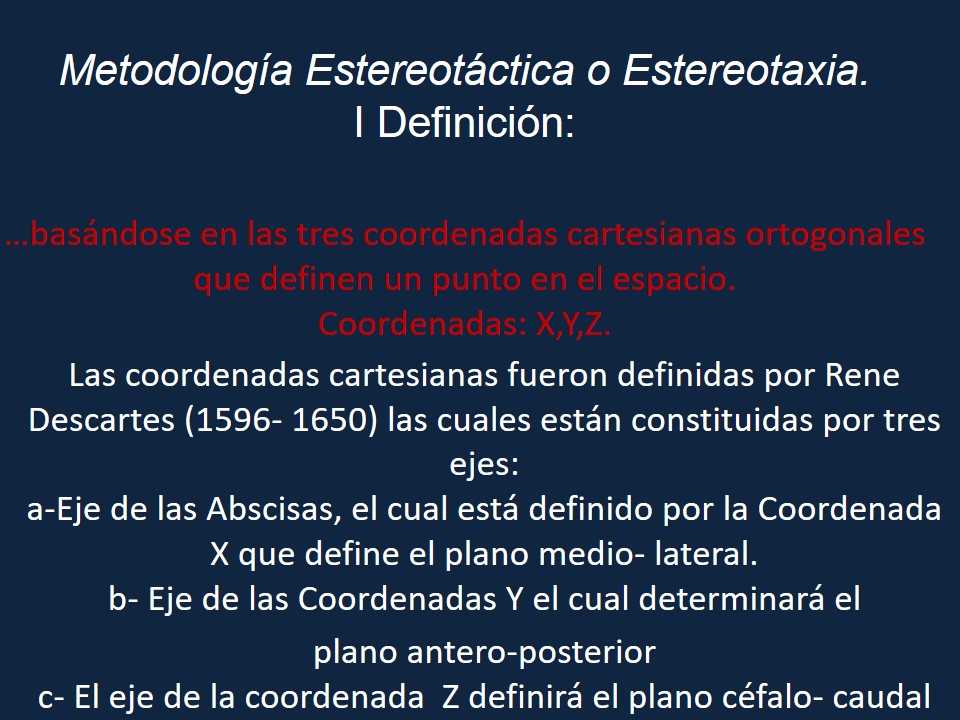

Metodología Estereotáctica o Estereotaxia